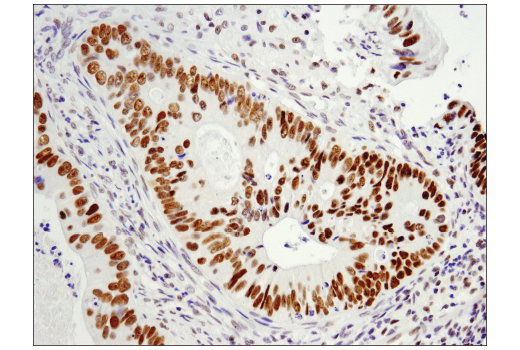

Immunohistochemical analysis of paraffin-embedded human endometrioid adenocarcinoma using LRF/Pokemon (D7U2O) Rabbit mAb.

Immunohistochemistry Image 3: LRF/Pokemon (D7U2O) Rabbit Monoclonal Antibody